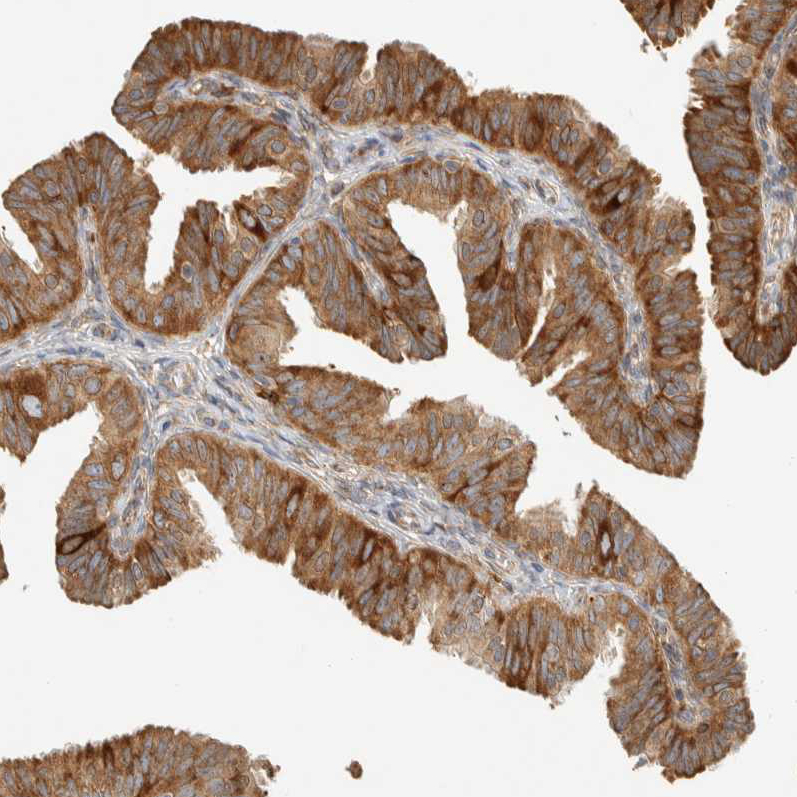

Immunohistochemical staining of human stomach shows moderate cytoplasmic positivity in glandular cells.